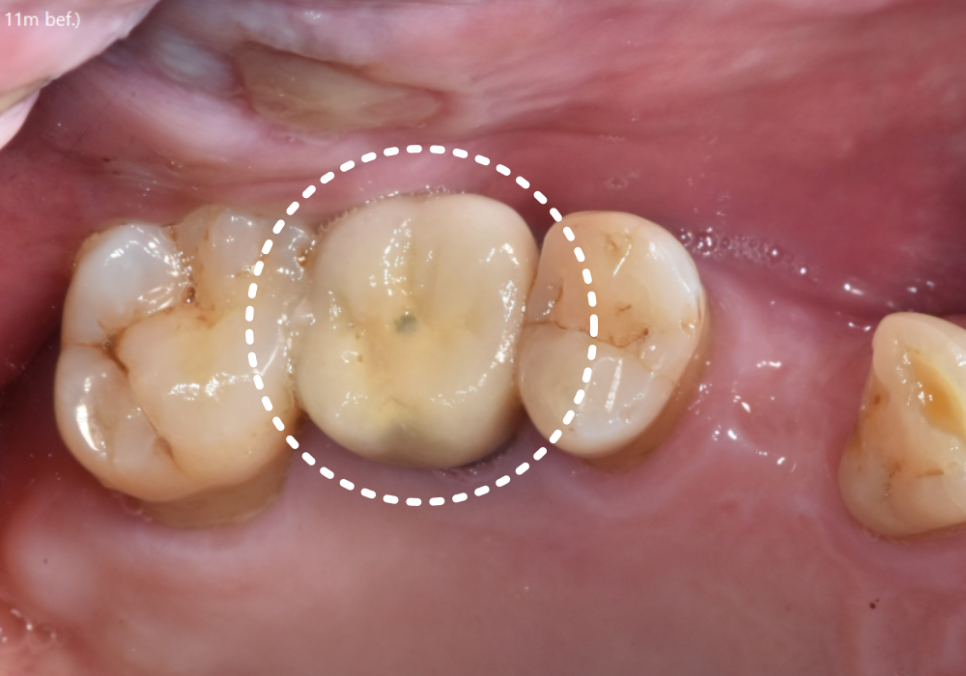

제거해 보니 다행히 내부 기둥은

멀쩡해 그대로 사용했습니다.

240614

덕분에 기둥을 새로 제작하지 않아,

환자분의 비용 부담은 줄일 수 있었어요.

도자기는 쓰다보면 겉의 도자기가 깨지는

경우가 종종 있어

더 튼튼하고 잘 깨지지 않는

'지르코니아'로 새로 제작해 드렸습니다.

이번에는 구멍이 없는 방식이 아니라,

씹는 면에 아주 작은 나사 구멍을 만들어는

'SCRP 방식'으로 변경했습니다.

240626

혹시라도 나중에 또 나사가 풀려도,

이제는 보철물을 뜯어내며

고생하실 필요가 없습니다.

구멍을 메워둔 재료만 살짝 걷어내고

드라이버로 1분 만에 조이면 끝나거든요.

꽤 간단하죠?